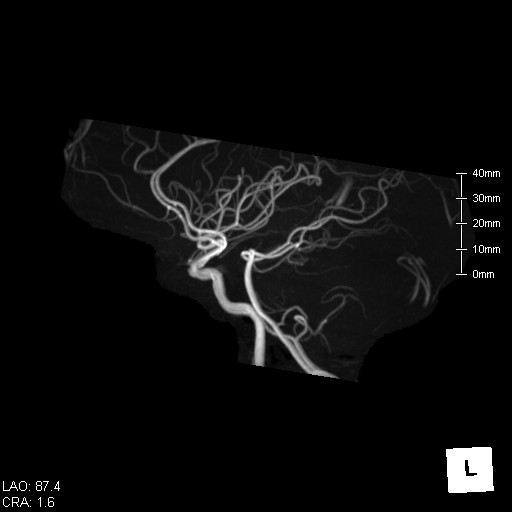

頭部の断面像 頭部の血管